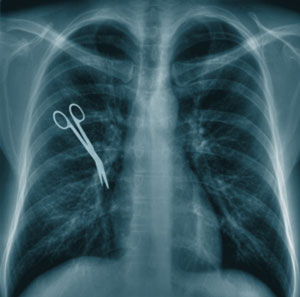

Top Injuries Claimed in Medical Malpractice Lawsuits

medicalmalpracticeI’ve written about our dysfunctional medical malpractice tort system before. In my opinion, attorney’s fees and court costs have a disproportionate stake in the economics of medical malpractice and health insurance in general, as opposed to what really matters: compensating the injured patient and disciplining the guilty doctor(s).

I decided to take a look at the top types of injuries claimed in medical malpractice cases submitted to LegalMatch.com in the past 12 months. Here is what I found: